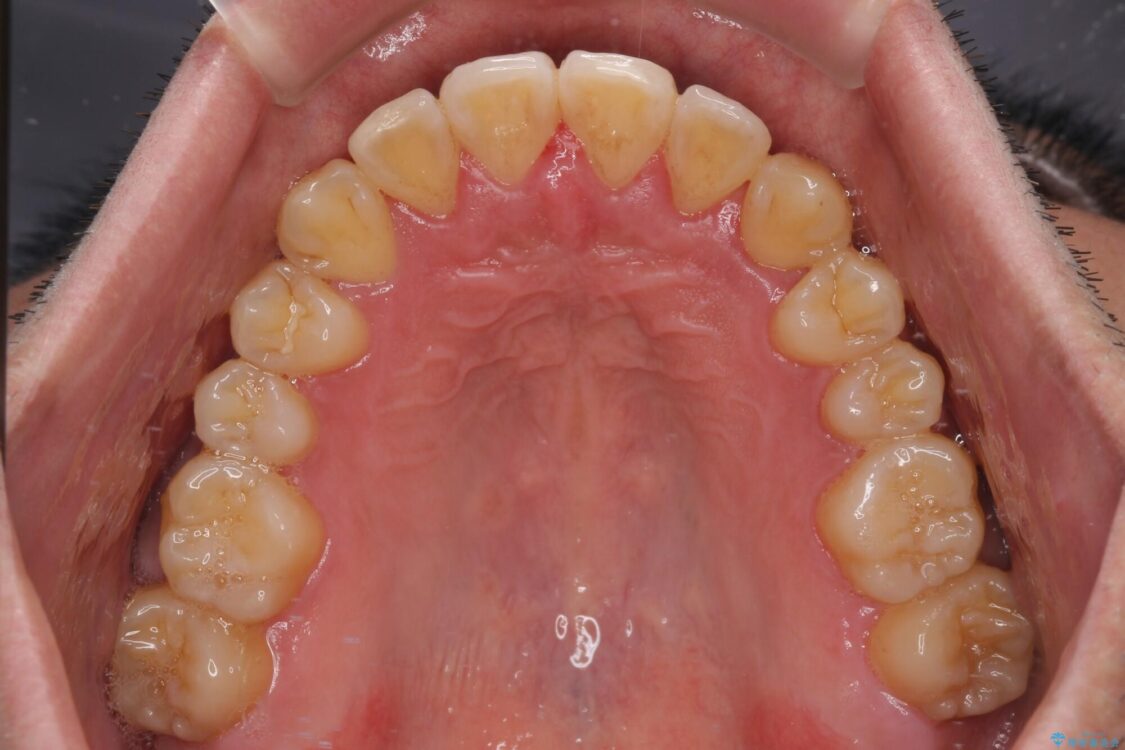

八重歯と前歯のクロスバイトを改善したいとのことで来院された患者様です。

デコボコの程度は強かったのですが、口元の突出感はなかったため、非抜歯矯正としました。

治療前

• 八重歯とクロスバイト 目立たないワイヤー装置で矯正治療 治療前画像